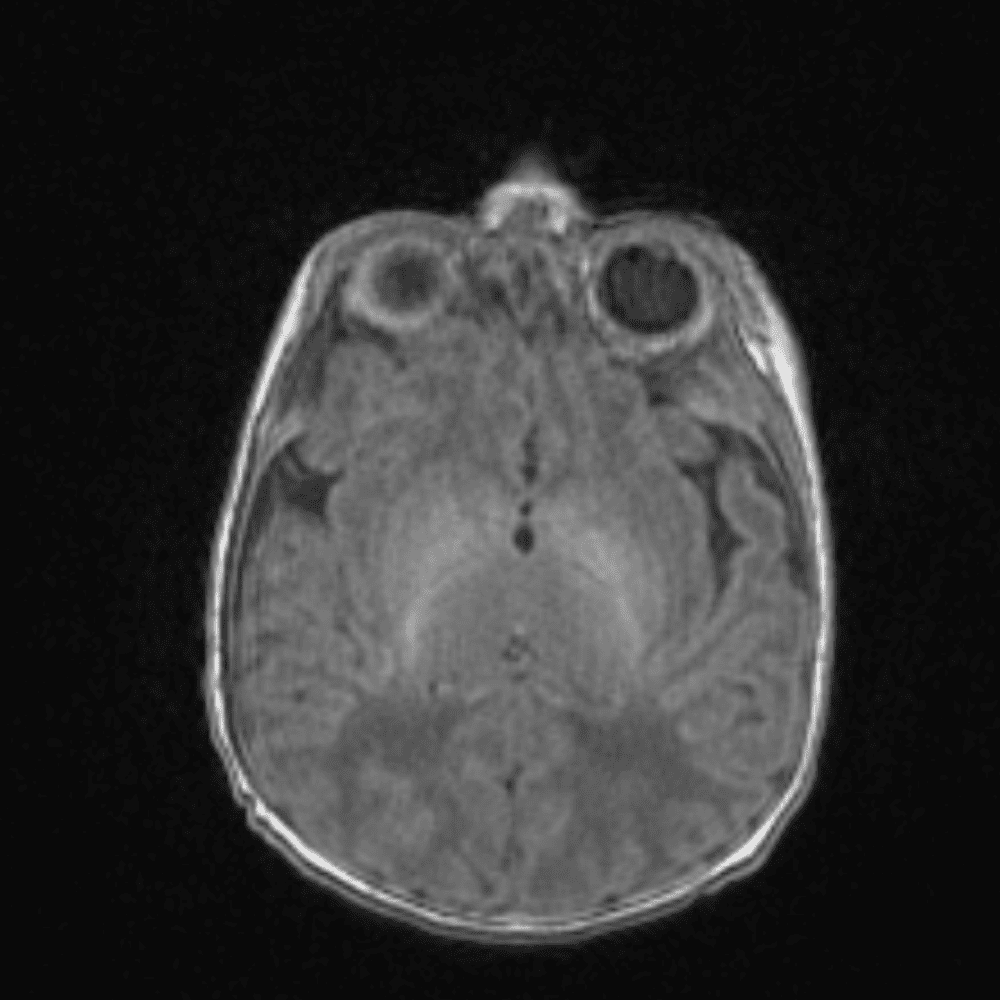

๋‹น์ง ์‹œ ํ”ํžˆ ๋ณผ ์ˆ˜ ์žˆ๋Š” ์‚ฌ๋ก€์˜ ์ „ํ˜•์ ์ธ ์˜ˆ๋ฅผ ํฌํ•จํ•ฉ๋‹ˆ๋‹ค.

39 ์‚ฌ๋ก€